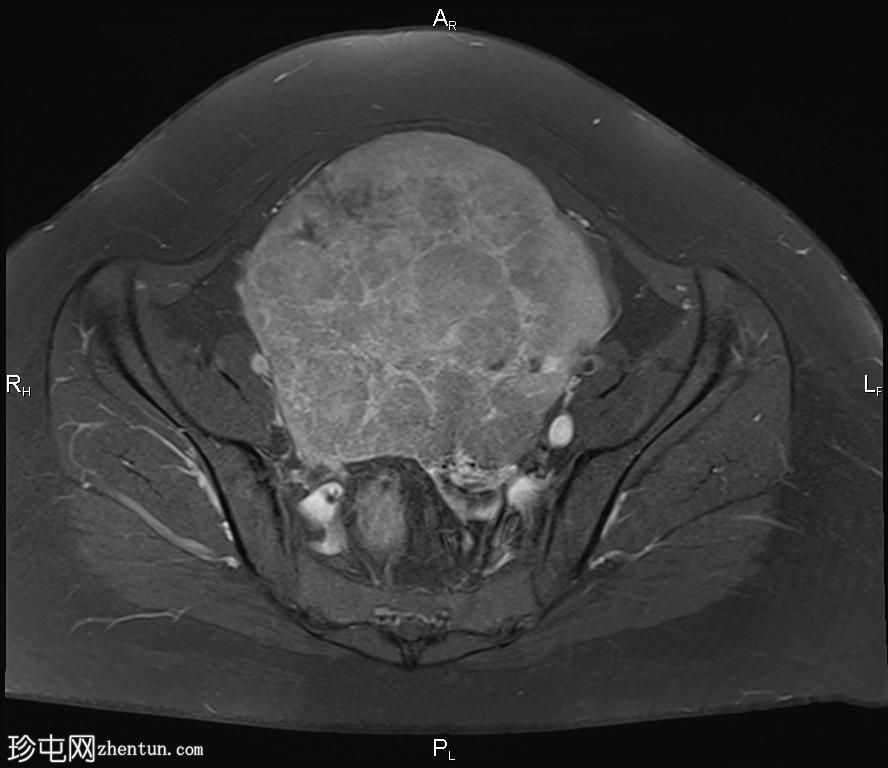

轴向位

T2

轴向T2

脂肪饱和度

盆腔内可见一巨大多分叶实性肿块,内部有隔膜,T2WI信号不均匀,T1WI信号不均匀,呈低信号。肿块内散在分布囊性/坏死性病变。

肿块外可见子宫和右侧卵巢,肿块似源自左侧卵巢。该肿块压迫膀胱和两侧远端输尿管,并导致肠管和血管结构移位,但无侵袭或包裹征象。

造影后,肿块呈不均匀强化,隔膜强化。

远端髂腹旁和两侧髂骨旁区域可见少量肿大淋巴结。